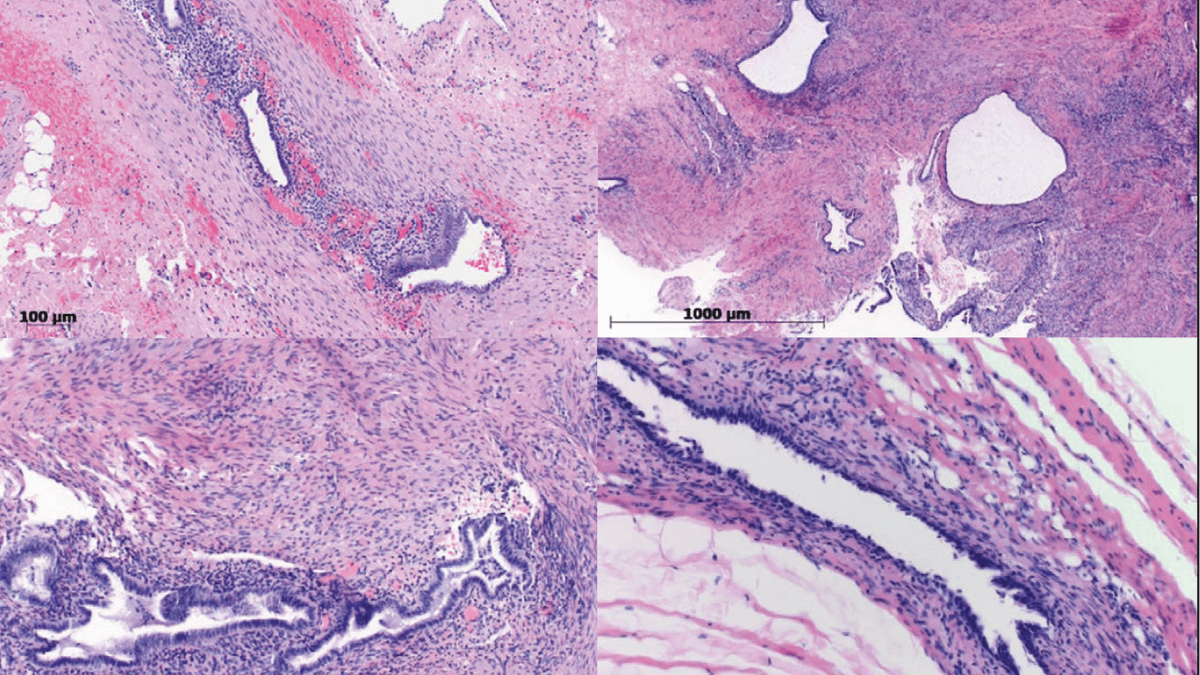

Verschiedene Erscheinungsformen der Endometriose lassen sich auch in der mikroskopischen Untersuchung des Gewebes erkennen.